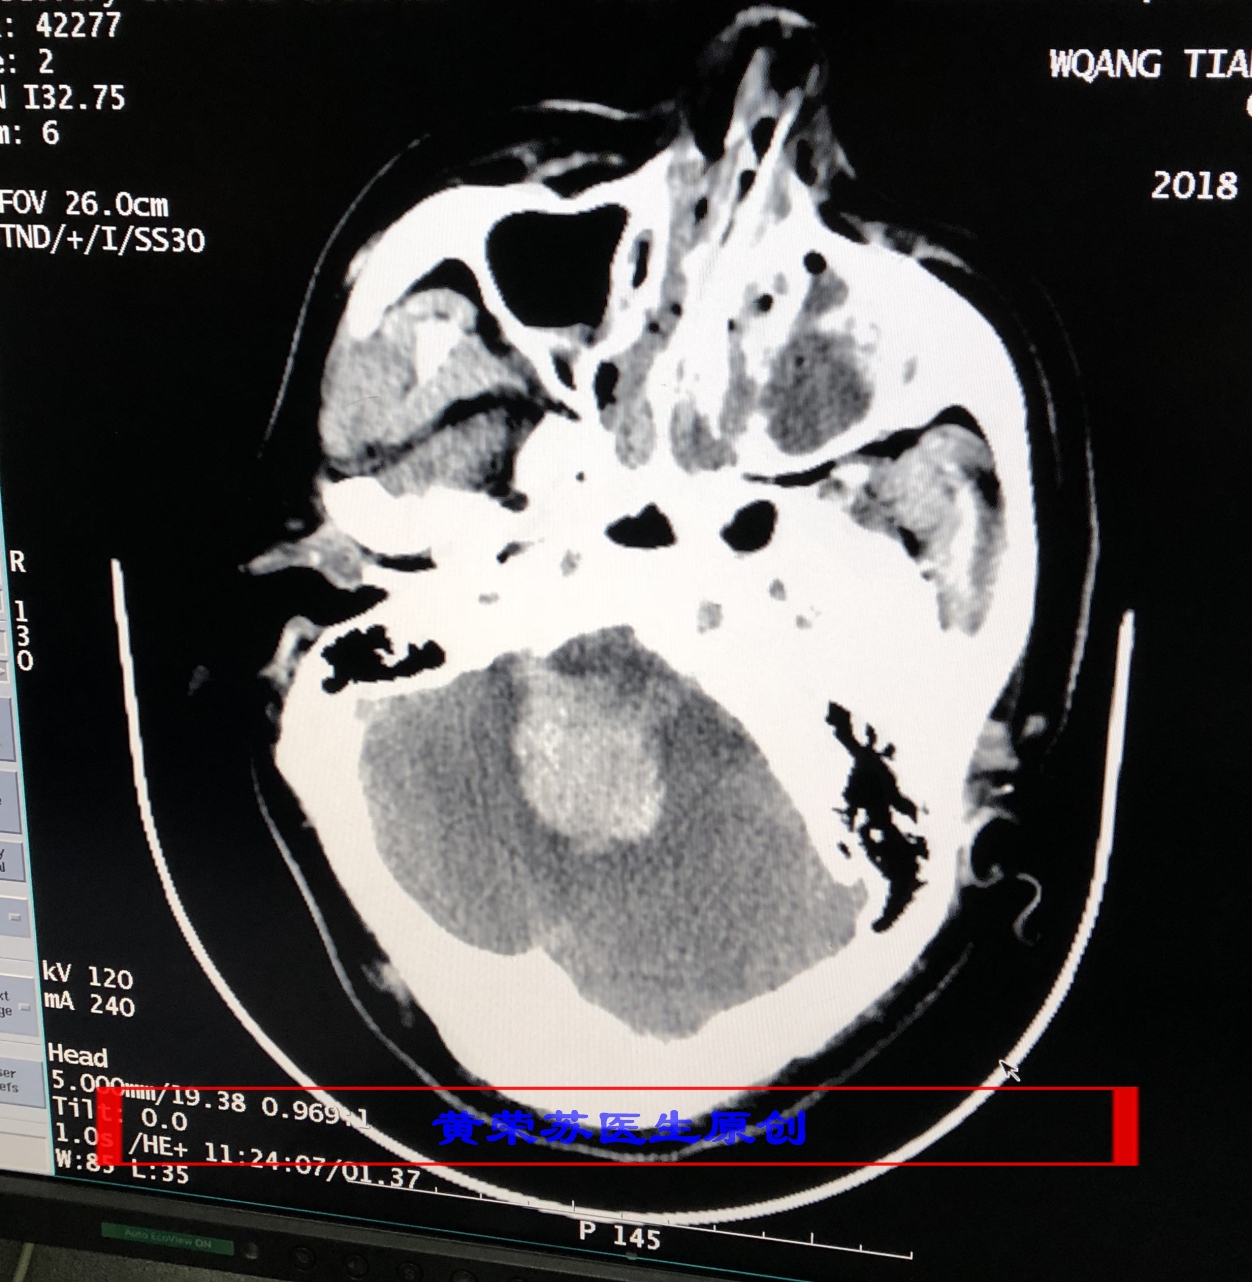

3、小脑出血:高血压脑出血又一常见部位,出血进展快,容易形成脑疝,死亡率高。多数表现为突发眩晕、频繁呕吐,枕部疼痛,一侧上下肢共济失调,眼球震颤,一侧周围性面瘫等。最常见于小脑齿状核动脉破裂所致。

图四、小脑脑出血